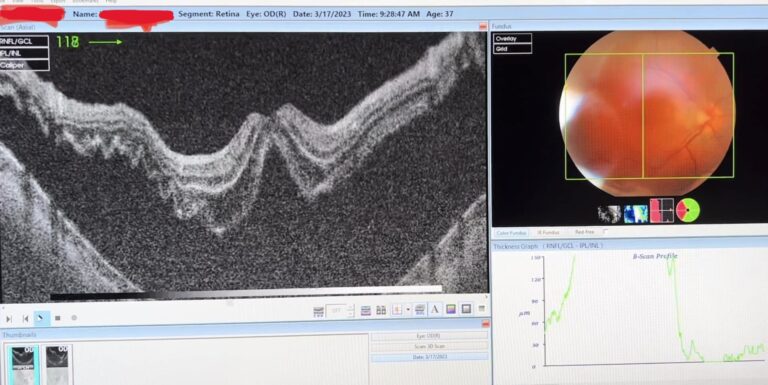

Iată povestea unei tinere paciente, operată pentru miopie forte (-27 dioptrii !!!) și care a venit zilele trecute la controlul postoperator de șase luni, extrem